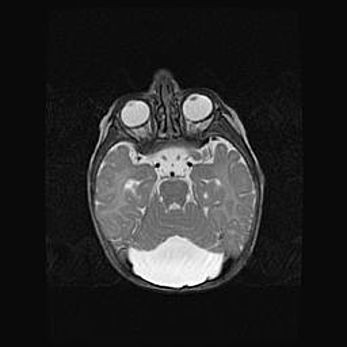

Церебральная ишемия II.

Возраст: 5 дней

Вес: 3400 г

Пол: женский

Окружность головы: 35 см

Срок гестации: 39 недель

Церебральная ишемия – это заболевание, характеризующееся недостаточностью (гипоксией) либо полным прекращением (аноксией) снабжения мозга кислородом по причине закупорки одного или нескольких сосудов. Это приводит к  что метаболическим расстройствам различной степени тяжести в тканях головного мозга, развитию коагуляционных некрозов и гибели нейронов.